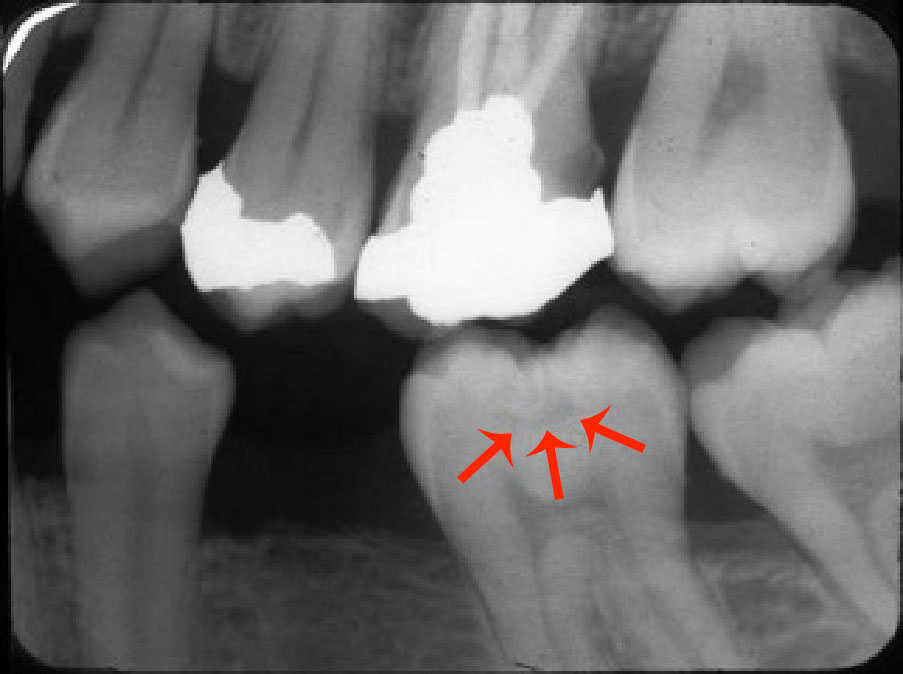

A carious lesion develops in three stages of demineralization. The first stage in demineralization of enamel is called the incipient lesion or “white spot” (Figure 1). This beginning carious lesion can be reversed with the daily use of fluoride or calcium and phosphate, persistent oral hygiene care, and a reduction of refined carbohydrates. The second stage involves the progression of demineralization leading to the DEJ and into the dentinal layer. The third stage is the actual cavitation in the dentinal layer. Neither of the last two stages can be reversed and require mechanical removal of dental caries.

When saliva is released into the oral cavity via the salivary glands, the pH of the saliva returns to normal or an approximate pH of 7 and a period of remineralization (repair) occurs. This process is facilitated if fluoride or calcium and phosphate ions are present locally. The balance between demineralization and remineralization is crucial. If the balance is not maintained and demineral­ization occurs too frequently, then an incipient lesion will occur. This incipient or ‘white spot’ lesion may take up to approximately 9 months or more to be seen via digital imaging or radiographically as a radiolucency or dark spot on a bite-wing radiograph.

Smooth Surface Caries and Interproximal Surface Caries (Figure 3). Includes Class V buccal, lingual surfaces of anterior and posterior teeth and Class II interproximal surfaces of all teeth below the interproximal contact points.

Figure 3. Smooth surface caries and interproximal surface caries.

Figure 3